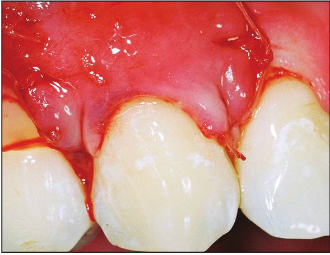

Cervical lesion treatment options of Connective Tissue Graft or Alloderm

| After |

Surgical treatment options for noncarious cervical lesion (NCCL)

Vertically coronally advanced flap (V-CAF) and connective tissue graft (CTG)

The traditional CT graft is still the gold standard for this procedure.